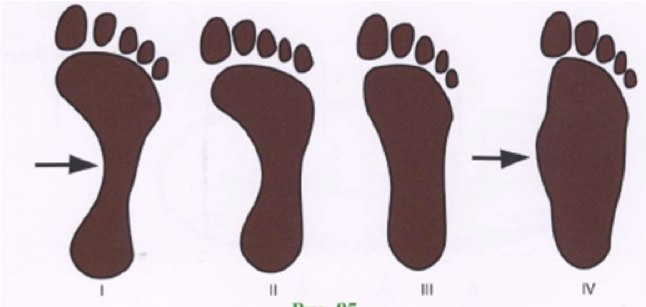

Тип стопы

Узнайте тип своей стопы, в том числе определите какой у нее подъем: низкий, нормальный или высокий. Если вы не уверены в том, какой у вас тип стопы, то проведите простой тест: окуните ногу в небольшую емкость с водой, затем поставьте стопу на лист бумаги, после чего посмотрите на оставшийся след.

Низкий свод: если стопа отпечаталась почти полностью, то у стопы низкий свод, и, вероятно, во время ходьбы или бега она будет иметь тенденцию склоняться внутрь. В таком случае вам, возможно, необходима обувь с контролем движений или повышенной устойчивостью.

Нормальный свод: если вы видите только половину свода, то у вашей стопы нормальная пронация. Это самый распространенный тип и, скорее всего, вам подойдет большинство моделей обуви.

Высокий свод: если вы увидите только отпечаток подушечки стопы и пятки, то у вашей стопы высокий свод. Вполне возможно, что в данном случае при ходьбе или беге стопа будет иметь тенденцию к повороту наружу. Выбирайте мягкую обувь с повышенной гибкостью, которая позволит более эффективно поглощать удары. Также приобретите специальные стельки для поддержки пятки и свода. Они, как правило, продаются отдельно и имеют различный размер и характеристики.

Пронация стопы

О пронации говорит количество точек соприкосновения стопы с поверхностью пола. Существует 3 основных типа пронации:

При чрезмерной пронации точки соприкосновения смещаются внутрь, а значит возникает риск растяжения мышц стопы и ног. Также при гиперпронации, как правило, у стопы низкий свод. Выбирайте обувь с повышенной устойчивостью и контролем движений, чтобы сгладить такие анатомические особенности стопы.

При недостаточной пронации (супинация) во время ходьбы или бега точки соприкосновения стопы с поверхностью земли смещены наружу. Как правило, в таких случаях у стопы высокий свод. Выбирайте обувь с дополнительной амортизацией, которая позволяет смягчать и поглощать удары.

При нормальной пронации точки соприкосновения распределены равномерно. Выбирайте обувь с повышенной стабильностью, которая является более гибкой по сравнению с кроссовками с контролем движений, но также обеспечивает хорошую поддержку.

Плоскостопия чаще всего бывает два, иногда три. Поперечное, продольное и их комбинация – продольно-поперечное.

Продольное плоскостопие можно выявить методом сравнения отпечатков стоп с шаблонами. Отпечаток можно сделать дома, намазав стопу краской и наступив на бумагу. Также диагностику стоп сейчас активно проводят во многих ортопедических салонах.